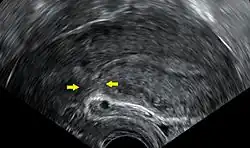

| Momento em que o bebé é retirado do útero durante uma cesariana | |